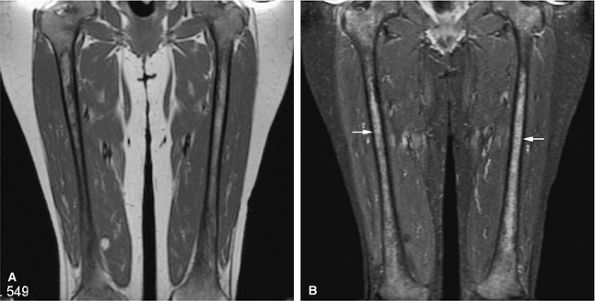

FIGURE 13.24 ● Abnormal bone marrow signal following administration of G-CSF. There is diffuse low signal on a coronal T1-weighted image of the thighs (A), which is hyperintense on the corresponding STIR image (B). G-CSF produces STIR hyperintensity, which can simulate diffuse marrow malignancies or leukemia (arrows). Bone marrow biopsy may be recommended in this situation.

|